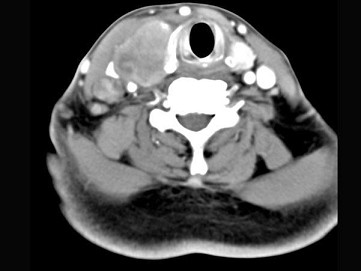

女,54岁,右侧颈部肿大近1年,近来病人有声嘶、吞咽困难,CT扫描如图,正确的描述或诊断是()

A.右侧甲状腺肿大,密度减低

B.增强扫描示甲状腺呈不规则强化团块影,其内有低密度区,病灶境界不清

C.右侧颈内静脉增粗,其内可见不规则充盈缺损区

D.甲状腺癌

E.右侧颈内静脉瘤栓形成

[多选题] 女,54岁,右侧颈部肿大近1年,近来病人有声嘶、吞咽困难,CT扫描如图,正确的描述或诊断是()A . 右侧甲状腺肿大,密度减低B . 增强扫描示甲状腺呈不规则强化团块影,其内有低密度区,病灶境界不清C . 右侧颈内静脉增粗,其内可见不规则充盈缺损区D . 甲状腺癌E . 右侧颈内静脉瘤栓形成

[多选题] 女,54岁,右侧颈部肿大近1年,近来病人有声嘶、吞咽困难,CT扫描如图,请选择正确的描述和答案()A . 右侧甲状腺肿大,密度减低B . 增强扫描示甲状腺呈不规则强化团块影,其内有低密度区,病灶境界不清C . 右侧颈内静脉增粗,其内可见不规则充盈缺损区D . 考虑甲状腺癌E . 右侧颈内静脉瘤栓形成

[多选题] 女性,54岁,右侧颈部肿大近1年,近来病人有声嘶、吞咽困难,CT扫描如图,请选择正确的描述和答案()。A . 右侧甲状腺肿大,密度减低B . 增强扫描示甲状腺呈不规则强化团块影,其内有低密度区,病灶境界不清C . 右侧颈内静脉增粗,其内可见不规则充盈缺损区D . 考虑甲状腺癌E . 右侧颈内静脉瘤栓形成